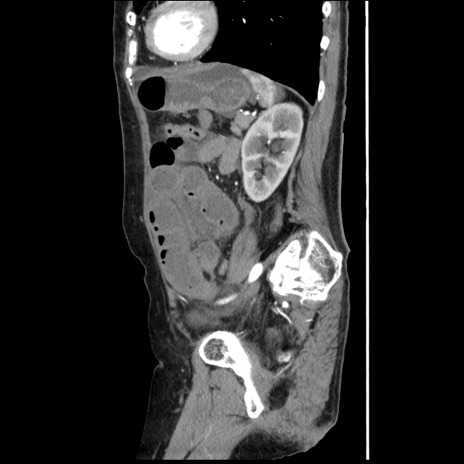

冠状断像

【症例】80歳代女性

【主訴】腹痛

【現病歴】8時間前から腹痛あり来院。

【既往歴】糖尿病、脂質異常症、子宮体癌にて子宮全摘術

【身体所見】意識清明・会話良好だが腹痛で苦悶様、全腹部にわたって反跳痛と圧痛あり

【データ】WBC 13600、CRP 0.14、LDH 224、CK 90